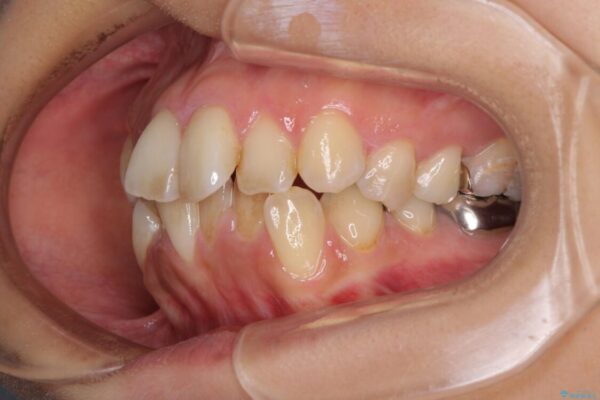

前歯のデコボコと上顎の前突感による口の閉じにくさを気にして来院された患者様です。

治療前

• デコボコと口元の突出感 ハーフリンガルでの抜歯矯正 治療前画像